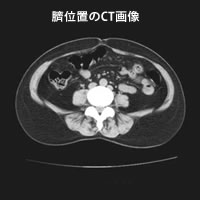

CT画像

• ct01

• ct02

• ct03

• ct04